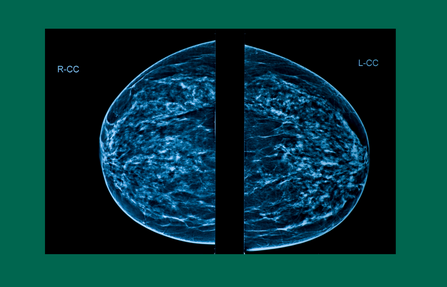

Dense Breast Tissue: What it means and why it matters

While breast density is not related to breast cancer survival, having dense breasts can make detecting cancer, especially in the early stages when it’s easiest to treat, challenging.